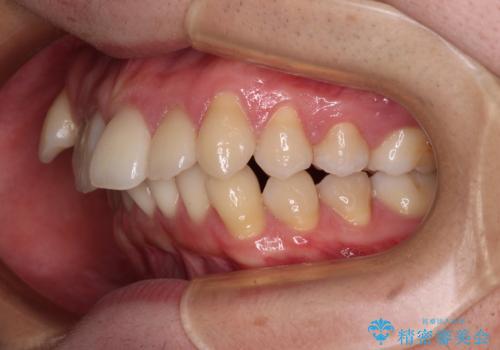

治療について

上顎のみの抜歯矯正であったため、治療期間が長期化することが予想されましたが、何とか3年弱の期間で想定通りの仕上がりで終えることができました。